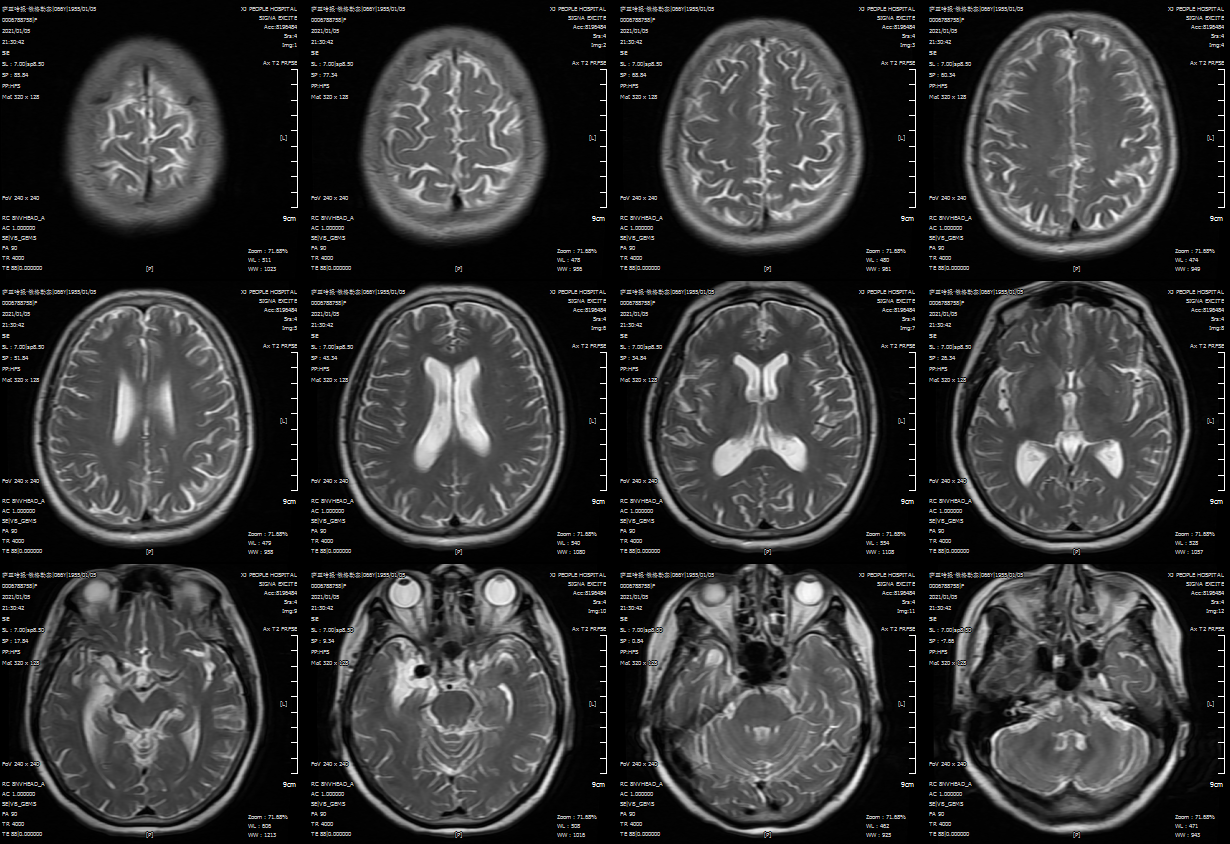

外院头颅MR示:右侧颞叶内侧血管流空影,考虑:颅内动脉瘤

朮后第二天复查头颅CT:颅内未见明显异常!